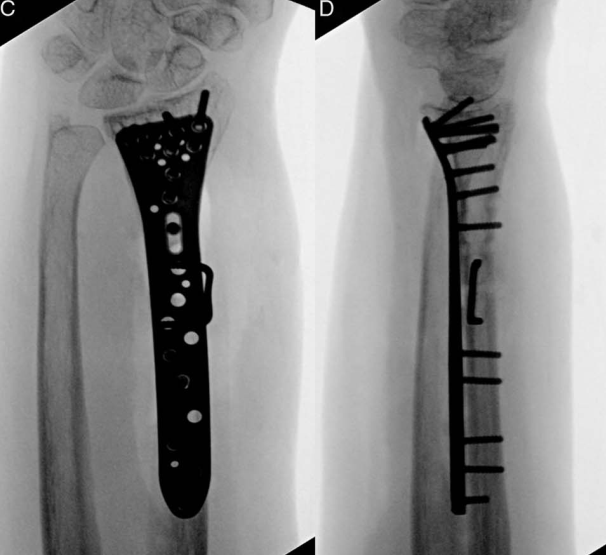

与肱骨干骨折相似,在桡骨干横行骨折的固定中,也可采用骑缝钉临时固定后,再通过钢板螺钉系统确切固定: